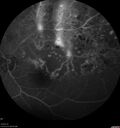

Branch Retinal Vein Occlusion - Both Eyes - Edema OD and NVE OS - Severe Non-perfusion Both Eyes324 views83 year old man with vision loss for 3 months not sure which eye. VA 20/100 OD and 20/50 OS. Tried avastin once without much improvement in the right eye and then lost to follow-up. FA in the left eye shows leaking NVENov 30, 2020

|

Branch Retinal Vein Occlusion - Both Eyes - Edema OD and NVE OS - Severe Non-perfusion Both Eyes369 views83 year old man with vision loss for 3 months not sure which eye. VA 20/100 OD and 20/50 OS. Tried avastin once without much improvement in the right eye and then lost to follow-up. FA in the left eye shows leaking NVENov 30, 2020